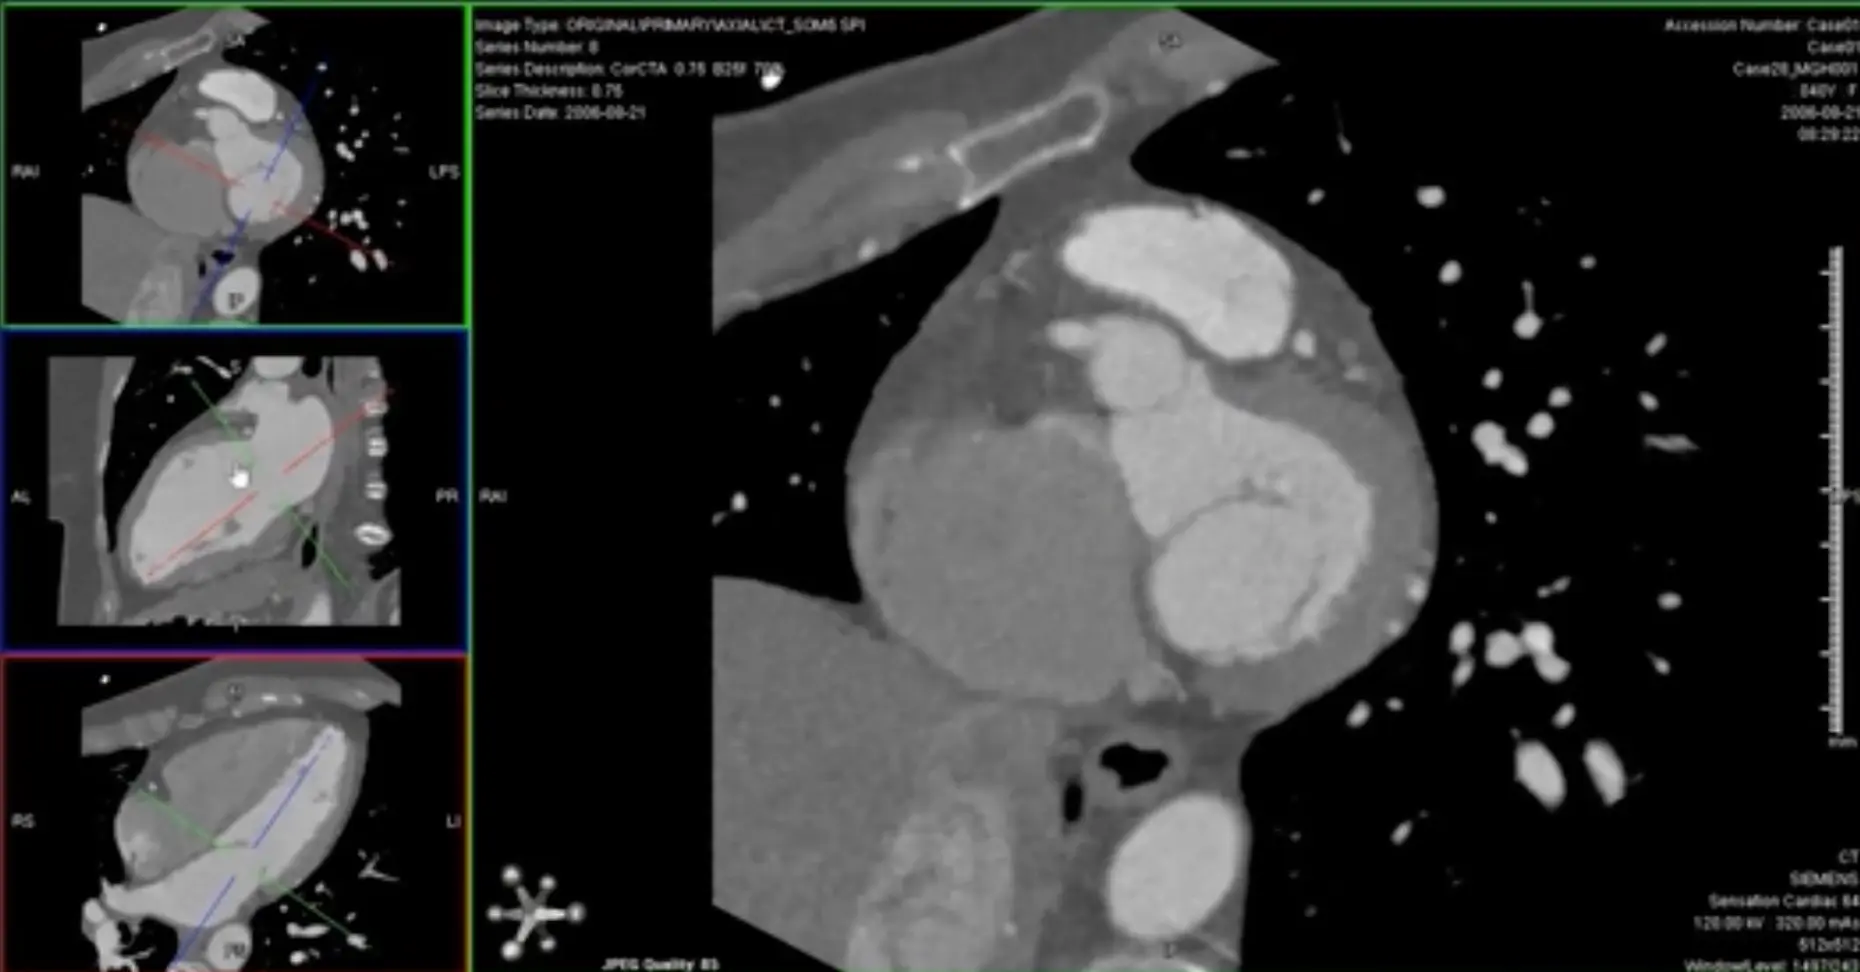

Cardiac Chamber evaluation

Left Heart

- On axial view, line up the ⌖ so that it is centered at the level of the mitral valve and the line goes through the LV apex

- In the remaining window where the LV looks like it is in the 2-chamber view, also line up the ⌖ so that it is centered at the level of the mitral valve and the line goes through the LV apex

-

The remaining third window is now our short axis (SAX) view → scrolling through this window gives you the SAX orientation of the LV (similar to Cardiac MRI)

- Scroll through from apex → base (or base → apex, if you’d like) and examine the LV cavity, filling defects, structural abnormalities, integrity of the ventricular septum